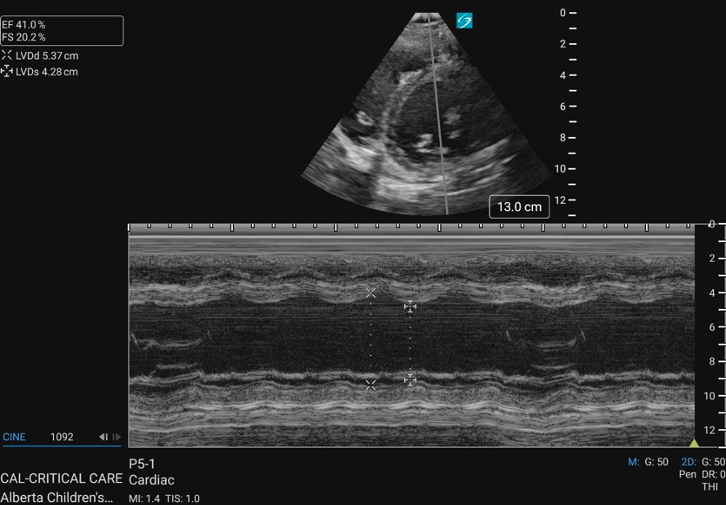

PSAX M-Mode

At the mid-papillary level, placing M-mode across the LV walls produces a motion trace of the septal and posterior walls throughout the cardiac cycle with distance displayed on the y-axis and time on the x-axis. The tracing shows the walls coming toward each other during systole and moving apart during diastole, with the LV cavity changing width in between (figure 15).

Figure 15: M-mode of the PSAX mid-papillary level

This pattern forms the basis for calculating fractional shortening (FS), which describes how much the LV diameter decreases during contraction, and linear EF, which measures volumetric change(figure 16). The FS and EF can be used to semi-quantify LVfx.

Measurements for FS and linear EF should be obtained at a single timepoint along the x axis corresponding to end-diastole and end-systole, rather than by selecting maximal wall excursion at different timepoints. Measuring the septum and posterior wall at different points of maximal excursion can result in inaccurate LV dimensions and overestimation of systolic function. It is also imperative to avoid placing the M-mode cursor through the papillary muscles, to ensure the true endocardial excursion is captured.

FS: percentage decrease in the LV diameter during contraction

Figure 16. LVIDd and LVIDs caliper placement for FS/EF calculation in PSAX M-mode

PSAX M-Mode Technique

1. At the mid-papillary level, place the M-mode curser perpendicularly through the centre of the LV cavity, between the papillary muscles

2. Measure the FS if findings appear grossly abnormal, when a quantitative baseline is useful for follow-up or clinical reassessment, or consultation with cardiology is anticipated.

– Select the FS calculation package and measure the left ventricular internal diameter in diastole (LVIDd) and in systole (LVIDs)

3. Save the M-mode image, and include the measurement if performed.

Note: FS M-mode can also be done in the PLAX view, by placing the M-mode cursor just past the MV leaflet tips; however, it is simpler and preferred in the PSAX view due to better alignment of the M-mode cursor perpendicular to the LV walls, which ensures more accurate and reproducible measurements.

What is Normal & Not Normal

- Normal values for FS in infants and children are typically between 28% and 46% [18,22] (figure 17).

- A FS <28% is generally considered abnormal. This can be further categorized into mild, moderate and severe systolic dysfunction (table 3) [22] (Figure 18).

- In pediatrics, normal EF is ≥ 55% (figure 17)[23].

Figure 17. PSAX M-mode normal FS and EF

Figure 18. PSAX M-mode abnormal FS